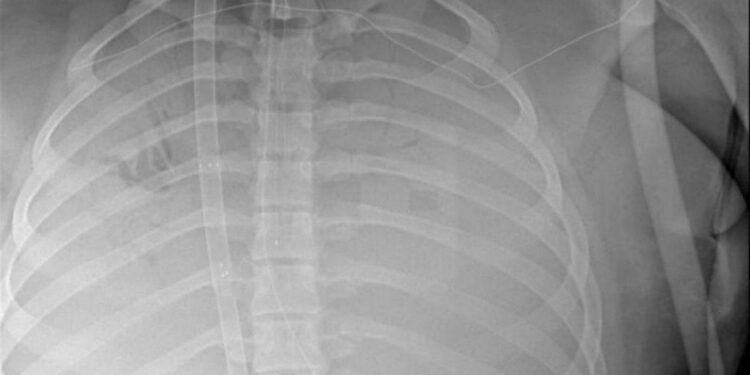

La paciente presentó dificultad respiratoria aguda, por lo que el 9 de noviembre fue intubada y se inició la oxigenación por membrana extracorpórea (ECMO, por sus siglas en inglés), una técnica que se aplica a pacientes cuyos pulmones o corazón están gravemente dañados. La niña mejoró con una combinación de antivirales, terapia renal continua e intercambio de plasma. No se le retiró la intubación hasta el 28 de noviembre, y la ECMO hasta el 22 de noviembre.